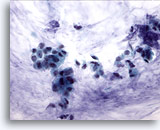

Figure 2

Breast FNA, Benign ductal cells.

Normal breast aspirates yield benign ductal cells, often accompanied by myoepithelial cells. 40x

Figure 2

Breast FNA, Benign ductal cells.

Normal breast aspirates yield benign ductal cells, often accompanied by myoepithelial cells.

40x